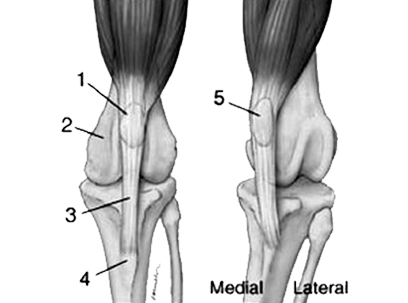

膝蓋骨「1」が正常の位置 膝蓋骨「5」がずれている

uxating patella – Wikipedia, the free encyclopediaより転載

何れにしても膝蓋骨脱臼の手術を行う時には、各々その関係する解剖を知ることから始めると良いでしょう。特に重要なのは、縫工筋と大腿四頭筋群です。大腿四頭筋とは大腿の前面にある大きな筋肉で、大腿骨の周囲にある筋肉です。これは大腿骨の周囲に存在する筋肉の総称です。大腿四頭筋には大腿直筋、外側広筋、内側広筋、中間広筋が含まれます。これに対して、ハムストリングスとは大腿の後の筋肉のことで、大腿二頭筋、半腱様筋、半膜様筋をいいます。これらのハムストリングスは大腿四頭筋とは主働筋・拮抗筋の関係にあります。